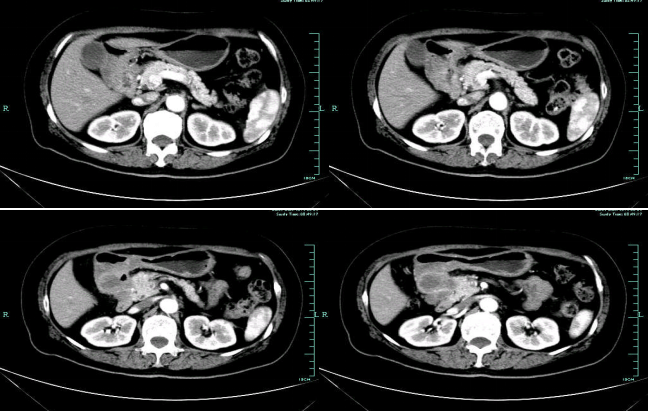

影像学表现:

• CT示:肝转移

• MR示:

CT-T

CT-H1

MR-H1

影像学检查结果评估:cPD。